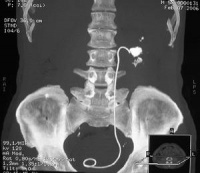

90%以上的输尿管结石在尿路平片上可被显示,草酸钙显示最佳,但需与腹腔淋巴结钙化盆腔静脉石阑尾粪石和骨岛角相鉴别。静脉尿路造影主要了解结石的部位和肾功能与有无积水,必要时行大剂量尿路造影及放射性核素肾图检查,均能进一步了解肾功能情况。膀胱镜检查与输尿管插管在结石处受阻,并拍平片钙化阴影在导管的同一平面,即能肯定输尿管结石的诊断。阴性结石用空气为对比剂作逆行造影摄片,则可显示结石的存在。另外CT及B型超声检查有助于对X线平片不显影结石的诊断。

2.泌尿系X线平片:在输尿管的途径上显出结石影。

3.尿路造影:在输尿管内显出结石影。

5.超声检查:在输尿管行程上显出结石。